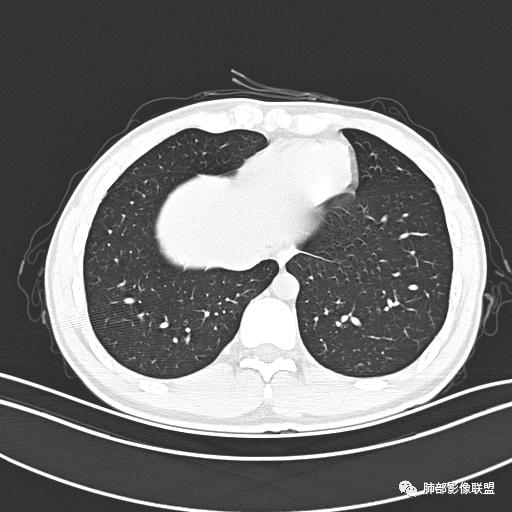

小强:青年,发热,皮疹;双肺散在结节,周围磨玻璃,点晕征,疱疹病毒感染,鉴别荚膜组织胞浆菌,结核。 大雄:青年,急性起病,发热伴全身皮疹2天,抗病毒治疗体温有下降。双肺随机分布大小不等类圆结节,“点晕征”。考虑水痘-疱疹病毒(VZV)血播询问接触史,查体皮疹分布以及形态基本可诊断。 王开金江津中心医院呼吸科:青年男性,起病急,病程短,以发热,皮疹为首发症状,感染指标以单核细胞升高为主,胸部ct双肺多发结界,周围有晕,点晕表现,随机分布,同意於老师意见,水痘疱疹病毒血流感染累及肺。 王秀仙:双肺多发大小不等结节,周围有晕,边缘模糊,呈点晕征表现。青年,急性起病,发热伴全身皮疹2天,抗病毒治疗体温有下降。考虑疱疹病毒。鉴别荚膜组织胞浆菌。 傅昌瑜:19岁男性,发热、全身皮疹2天,单核细胞增高,双肺多发结节,结节边缘见边界不清磨玻璃影。点晕征+发热、全身皮疹+单核细胞增高——考虑水痘-带状疱疹病毒肺炎。 一切∮随缘:年轻男性,发热,皮疹两天,实验室,CRP,PCT增高,影像:双肺多发散在磨玻璃结节,边界欠清,大小不等,呈点晕征改变,以血管束周围分布为主,局部血管束略增粗,其它无明显改变,考虑:1:病毒性肺炎(水痘疱疹病毒?不知道皮肤有无改变)2:真菌(组织胞浆菌,血管侵袭性肺曲霉)3:GPA4:寄生虫(实验室没有看到嗜酸细胞增高) 赵山河:双肺散在结节,周围有晕,边缘模糊,呈点晕征表现。青年,急性起病,发热伴全身皮疹2天,抗病毒治疗体温有下降。考虑水痘—疱疹病毒感染。洪桥爱:青年男性,发热、皮疹2天,伴瘙痒,皮疹于面部首发,之后进展至全身,虽然没有对皮疹进行描述,但是从出疹时间及皮疹进展情况,伴瘙痒,应该就是个水痘患者;CT提示双肺随机分布结节影,部分结节伴有边界不清晕征,考虑水痘血播肺。 刘强:年轻男性,急性起病,皮疹,发热,抗感染治疗体温下降,说明有效。影像表现为散在点晕征,感染类疾病谱(疱疹病毒,真菌,结核),结合年龄,皮肤皮疹,考虑水痘-疱疹病毒性肺炎。 小兜:男性,19岁,发热皮疹两天,颜面部至全身,CRP,降钙素及单核增高。CT示双肺散在小结节,周围伴磨玻璃影,点晕征,考虑为水痘-带状疱疹病毒(varicella-zoster virus,VZV)肺炎 必有路:青年,皮疹+发热+“点晕征”→水痘-疱疹病毒(VZV) 许慧良:青年男性患者,发热、皮疹2天,体温最高38.5℃,第3天皮疹扩展至全身,伴瘙痒,胸部CT:双肺多发随机分布的小结节,结节周边见边界模糊的晕征,考虑水痘病毒感染流心明智:男,19,急性起病,发热伴全身皮疹2天。出疹顺序头→全身,抗病毒有效。胸部CT:两肺多发大小不等类圆形实性小结节影,随机分布,结节周围环绕GGO,边界模糊,呈点晕征。出疹特点是关键,未提示。考虑:血播病毒性肺炎,水痘-疱疹病毒?麻疹?鉴别荚膜组织胞浆菌、TB、血管炎、寄生虫等。 浪迹天涯:病灶多为5-10mm大小结节,结节周围可见磨玻璃样的晕环,常多发,可分布于肺内任何区域,考虑水痘—带状疱疹病肺炎如果短时间内有新的一个区域浸润,更加能说明,